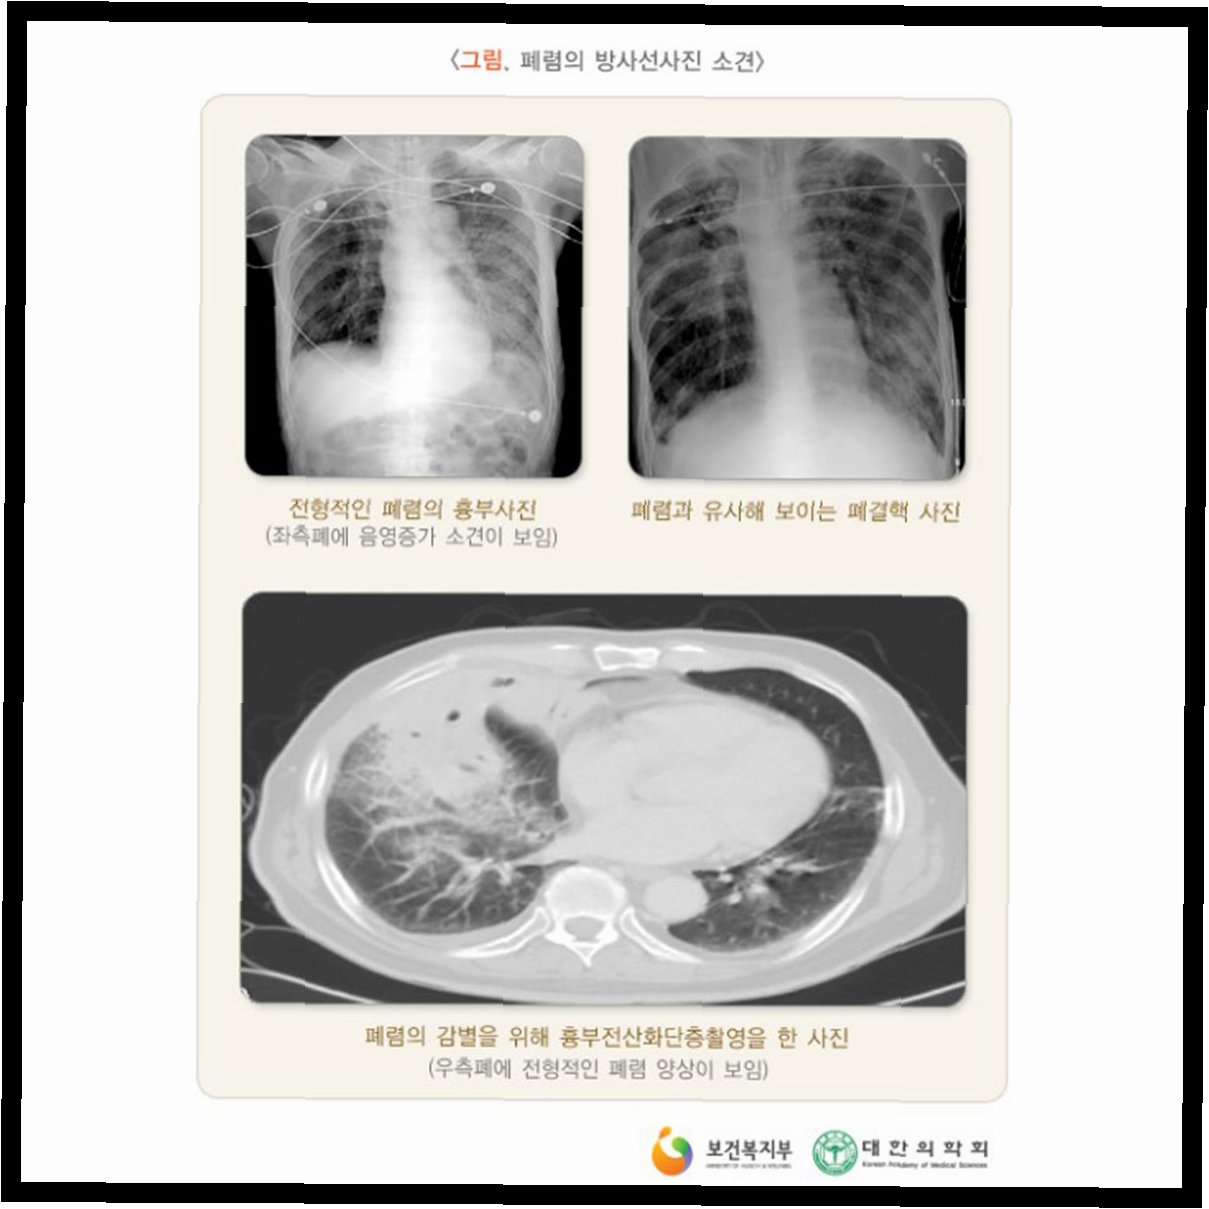

그간 흉부 방사선 검사는 주로 폐결핵 발견을 목적으로 시행돼 왔으나, 실제 폐결핵 유병률은 0.04% 수준에 머물러 왔다. 복지부에 따르면 2023년 기준 흉부 방사선 검사를 통한 폐결핵 발견율은 0.03%에 불과한 반면, 검진 비용은 연간 1426억원이 소요됐다. 이는 전체 국가건강검진 비용의 약 21%에 달하는 수치다.